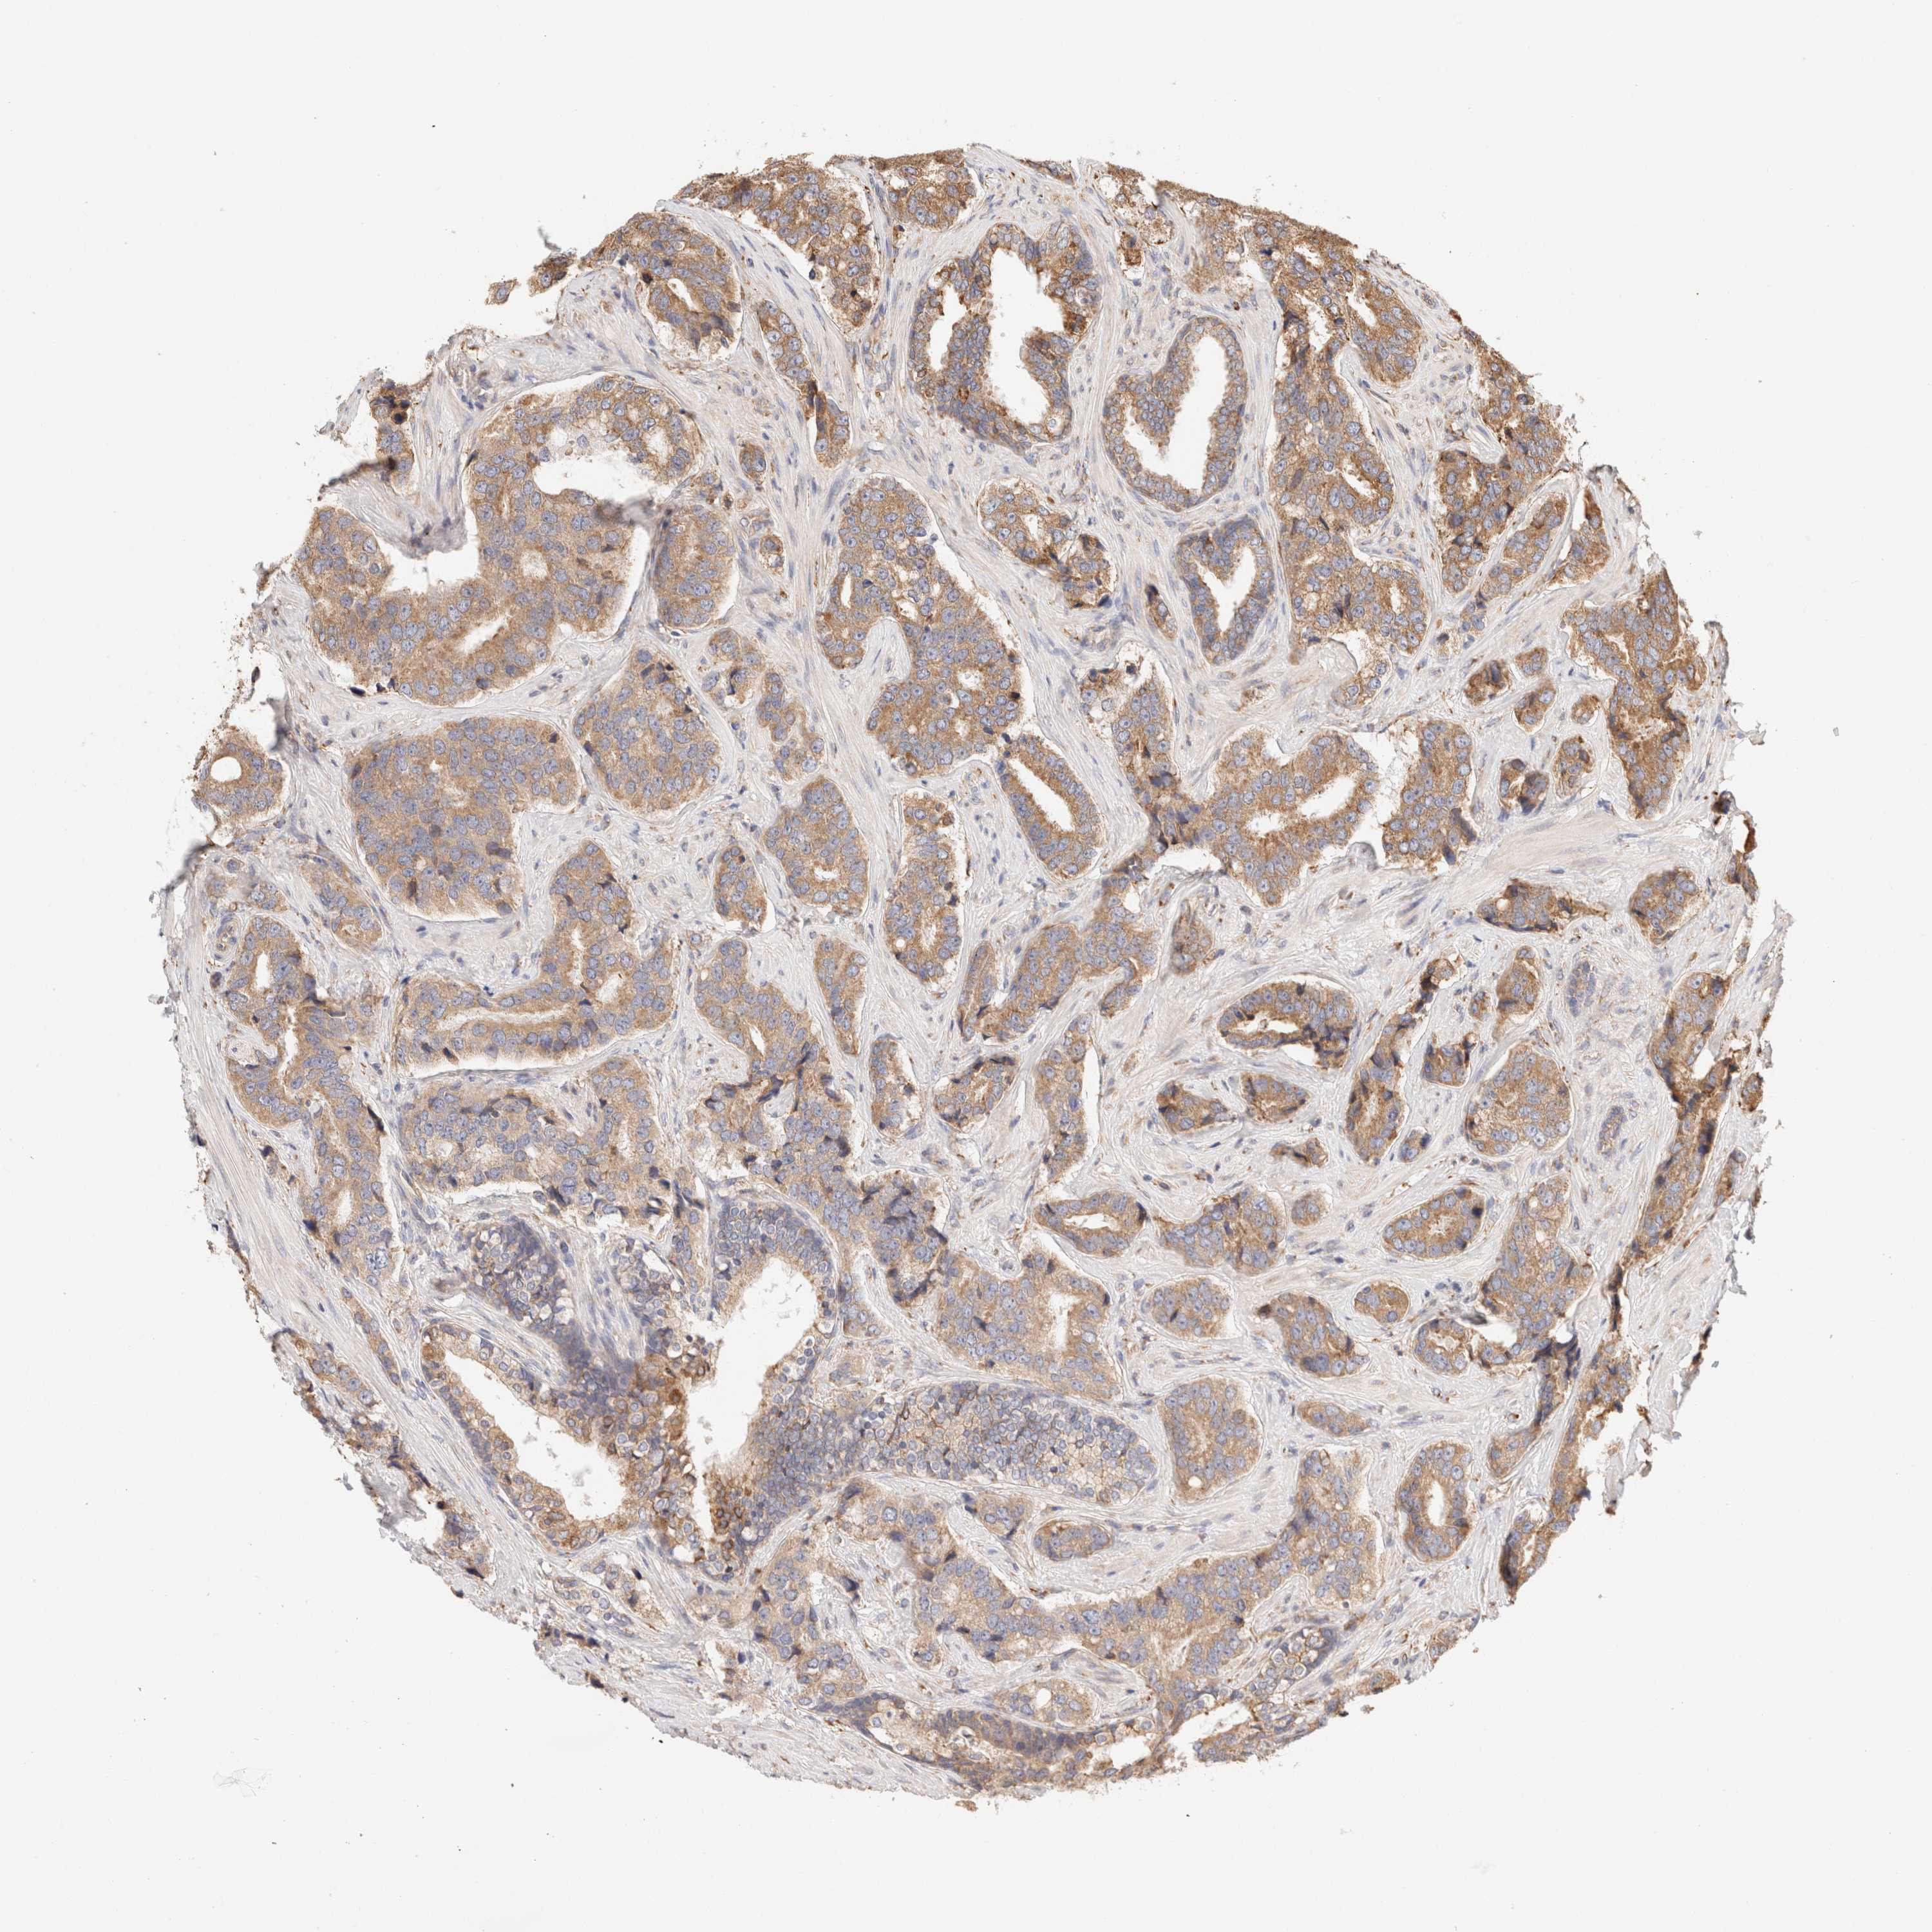

PROSTATE CANCER - Protein expressioni

A mouse-over function shows sample information and annotation data. Click on an image to view it in a full screen mode. Samples can be filtered based on level of antibody staining by selecting one or several of the following categories: high, medium, low and not detected. The assay and annotation is described here.

Antibody stainingi

Antibody staining in the annotated cell types in the current human tissue is reported as not detected, low, medium, or high, based on conventional immunohistochemistry profiling in selected tissues. This score is based on the combination of the staining intensity and fraction of stained cells.

Each image is clickable and will lead to virtual microscopy that enables deeper exploration of all samples and also displays staining intensity scores, fraction scores and subcellular localization as well as patient and tissue information for each sample.

Antibody HPA007641

Antibody CAB022464

Staining

High

Medium

Low

Not detected

Intensity

Strong

Moderate

Weak

Negative

Quantity

>75%

75%-25%

<25%

None

Location

Nuclear

Cytoplasmic/membranous

Cytoplasmic/membranous,nuclear

Adenocarcinoma, Low grade

Adenocarcinoma, High grade